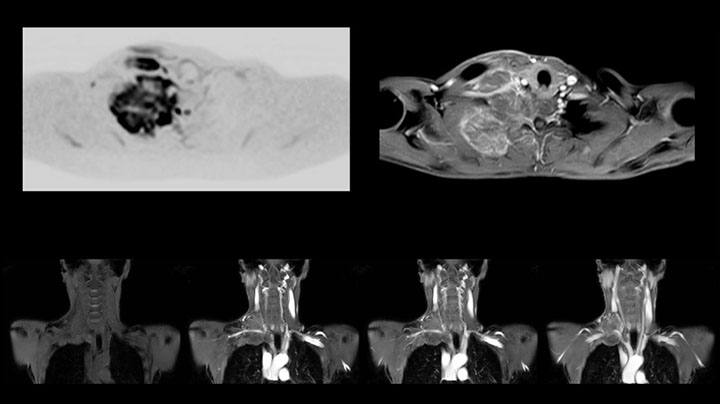

Although the area between the neck and the top of the lung is one of the most difficult areas for MRI, Prodiva 1.5T images show good quality in this 56-year-old male with Pancoast tumor on the right. mDIXON TFE images shows excellent fat suppression in the neck area and the DWI shows almost no distortion.